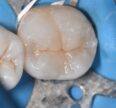

Simple fissurotomy and sealant using an A2 shade of Voco Grandio SO flowable and Voco Grandio SO paired with some Final Touch brown fissure tint. #VocoGrandioSO #GrandioSOflow #FinalTouchtint